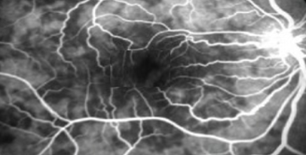

Dilated fundus exam shows geographic punched out yellow gray chorioretinal lesions in both eyes (Figure 1). The OCT shows lesions primarily in the outer retinal layers and choriocapillaris with increased reflectivity localized to the outer retina and disruption of the photoreceptor bands. There are a few older lesions demonstrated as atrophy and RPE disruption (Figure 2). Primary Care workup included chest x-ray, complete blood count, comprehensive metabolic panel, Interferon gamma release assay TB testing, angiotensin-converting enzyme/lysozyme, rapid plasma testing, syphilis antibody test, and herpes simplex virus 1 and 2 antibodies. All tests were within normal limits. This patient was diagnosis with idiopathic serpiginous choroiditis (SC) with foveal involvement in both eyes. The patient was also co-managed with a retinal specialist. The treatment plan included intravitreal triamcinolone 2 mg/0.05 mL OU with oral chlorambucil therapy immediately afterwards Active lesion resolved over the next 3 weeks, yet visual acuity showed no improvement as the foveal was already involved. The goal of chlorambucil therapy for 3 months was to induce sustained remission in Figure 3& 4.

Figure 3 Shows the right eye with hyperflurescent lesions areas indicating acute active disease. Angiogram (FFA) indicative.

Figure 4 Shows the left eye with scattered distinct lesion areas indicating acute active disease.